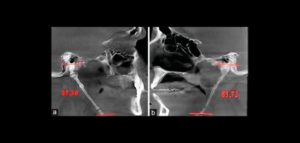

158 – Uso intraoperatorio de la CBCT para la identificación y localización de canales calcificados

Se sabe que la tomografía computarizada de haz cónico (CBCT) produce exploraciones tridimensionales de la dentición, las estructuras duras maxilofaciales y la relación de las